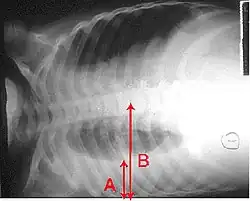

Right middle lobe pneumonia in a child as seen on plain X-ray